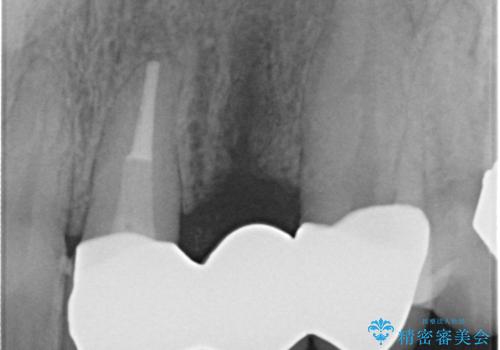

X線撮影や歯周組織検査から、クラウン下の虫歯の再発や歯の破折が疑われる状況でした。

左上2は、クラウン メタルコアの除去を行ったところ虫歯の再発や亀裂を認め、長期的な予後の期待が難しいことから抜歯を行い

ブリッジで審美性の回復を行っていく運びとなりました。